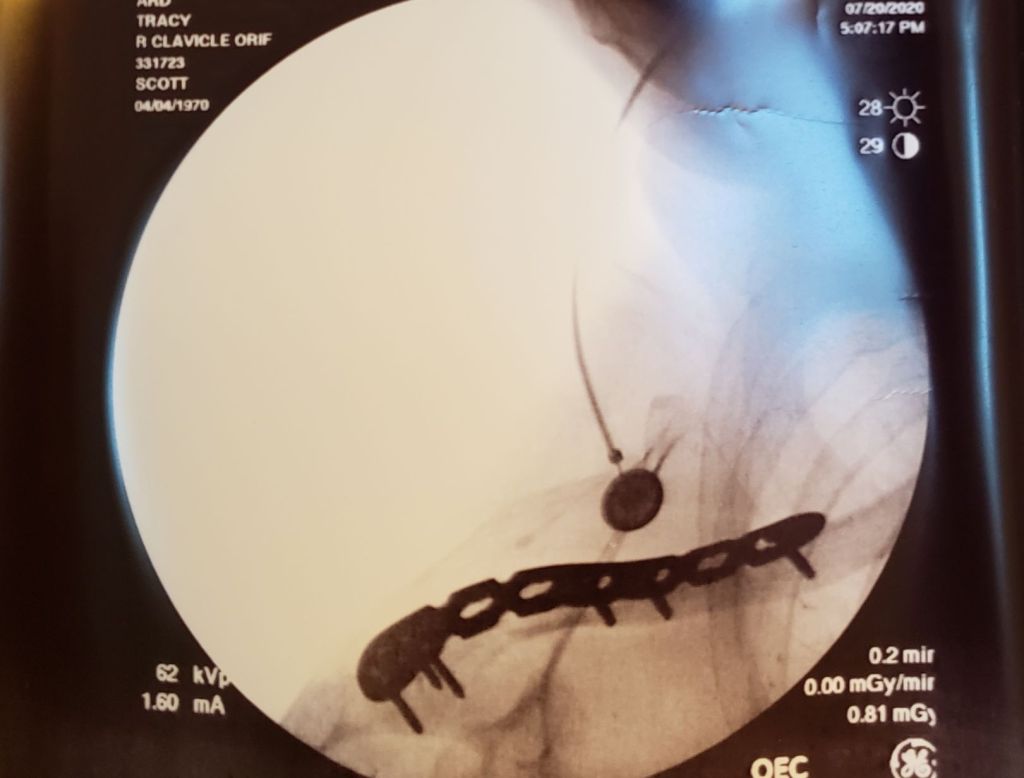

By the time he got back, loaded me into the car, and driven us within range of a cell tower so I could call and tell Tamie, my wife, that I wasn’t going to be home in time for lunch, it was 2pm. Then, it took us an hour to get to the hospital where I spent another hour in a wheelchair breathing through a mask in the waiting room with a bunch of sickos carrying COVID-19, chlamydia, and countless other communicable diseases that I imagined. The doctors then spent the next three hours hooking me up to an IV and scheduling a CT scan and taking x-rays and administering painkillers and, for reasons I still don’t understand, a tetanus booster, before they finally all agreed my collar bone should definitely not be jutting out from my shoulder like that.